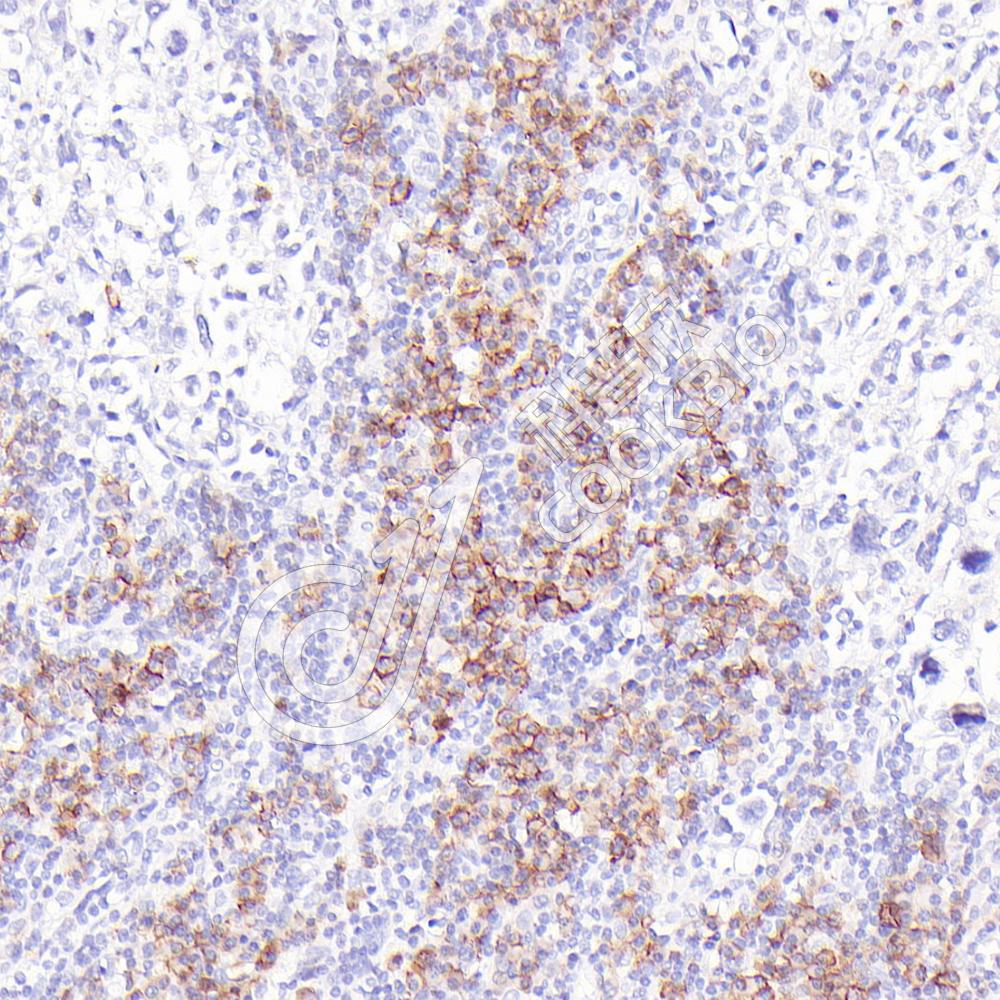

IHC检测CD32蛋白(货号 K1344499).

样品: 人弥漫性大B细胞淋巴瘤, 4%多聚甲醛 (货号KSG1101) 固定12-24小时.

抗原修复: 柠檬酸抗原修复液(干粉, pH 6.0) (KSG1201), 98℃, 20分钟.

—抗: 1: 600稀释, 4℃ 孵育过夜.

二抗: S-vision免疫组化多聚二抗(山羊抗兔),即用型 (货号KB3906), 室温孵育20分钟.